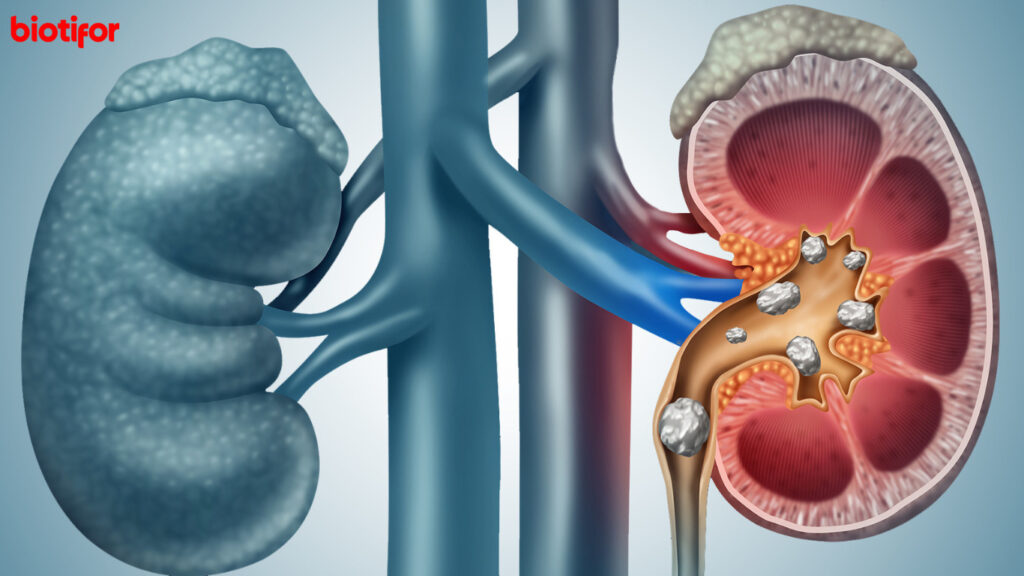

Batu ginjal ialah keadaan di mana material keras tercipta dalam ginjal dan menimbun jadi batu. Batu ginjal bisa terjadi saat beberapa zat tertentu dalam urine, seperti kalsium, oksalat, dan asam urat, mengkristal dan bersatu. Kristal-kristal ini selanjutnya bisa bergabung dan membuat batu yang bisa berbagai ragam ukuran, dari seukur biji pasir sampai seukur bola golf.

Batu ginjal bisa mengakibatkan beragam gejala, termasuk ngilu kronis pada bagian bawah punggung atau perut, dibarengi muntah dan mual. Disamping itu, batu ginjal bisa mengakibatkan darah dalam urine dan sering membutuhkan perawatan klinis.

Ngilu pinggang ialah gejala umum yang berkaitan dengan batu ginjal. Ngilu ini kerap kali terjadi pada bagian bawah punggung atau pinggang. Batu ginjal bisa mengakibatkan iritasi pada ureter (aliran yang menyambungkan ginjal dengan kandungan kemih), mengakibatkan merasa sakit tajam atau tumpul. Merasa sakit ini dapat benar-benar intensif serta menjalar ke sisi depan perut atau pangkal paha.

Batu ginjal yang membuat iritasi aliran kemih bisa mengakibatkan ngilu atau kesan kebakar saat membuang air kecil. Ini karena batu ginjal bisa membuat iritasi dinding ureter atau mengakibatkan infeksi di aliran kemih.

4. Urine Berwarna Gelap atau Berdarah

Batu ginjal dapat menghancurkan jaringan di sepanjang aliran kemih, yang bisa mengakibatkan urine warna gelap atau memiliki kandungan darah. Ini muncul karena ada pendarahan yang disebabkan karena gesekan batu ginjal dengan dinding ureter atau kandungan kemih.

Batu ginjal bisa bergerak di aliran kemih, mengakibatkan merasa sakit yang berfluktuasi. Merasa sakit dapat bertambah atau menyusut bergantung di posisi dan pergerakan batu ginjal.